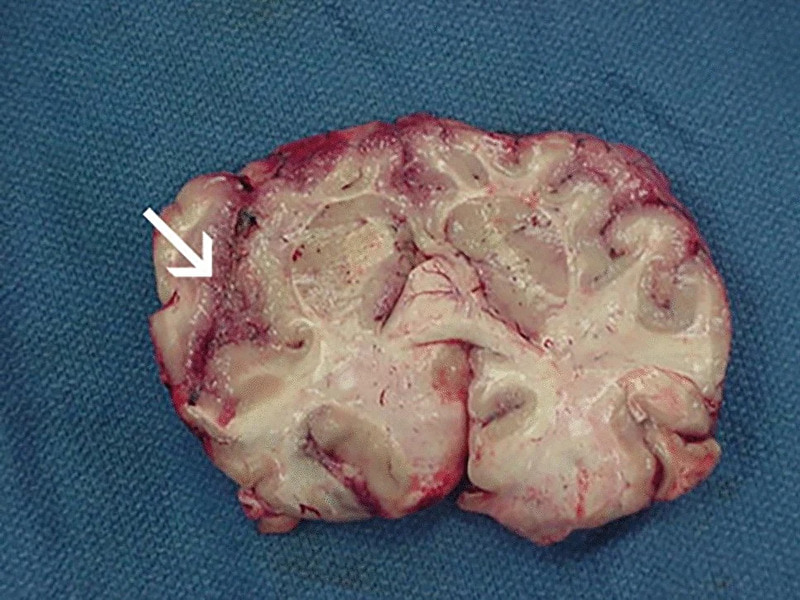

gif_animation アメリカではニュースで報道される事も多いという「脳食いアメーバ」こと「ネグレリア・フォーレリ」に感染した人々の画像や脳画像のまとめギャラリー。このアメーバが一次性アメーバ性髄膜脳炎(PAM)を引き起こした場合、致死率はほぼ100%だと言われている。感染経路は世界中に温かい淡水で、身近な所では「水道水で鼻洗浄」をした女性が亡くなった事例などがある。[13]images